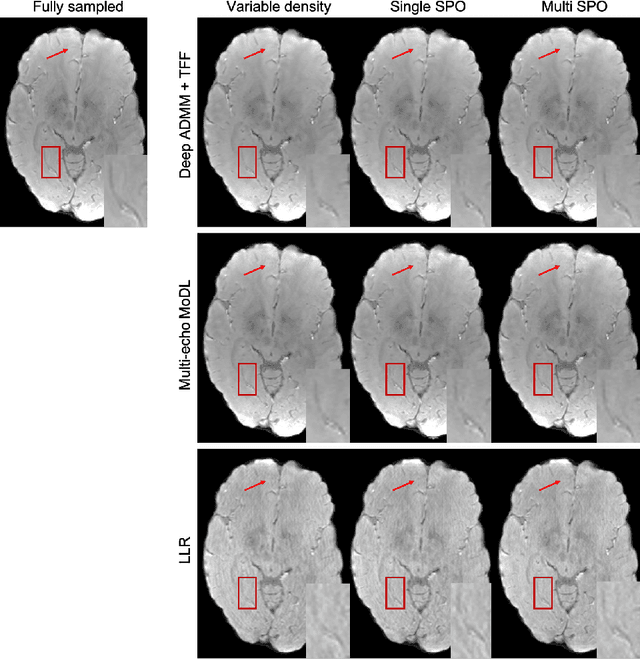

Abstract:Quantitative imaging in MRI usually involves acquisition and reconstruction of a series of images at multi-echo time points, which possibly requires more scan time and specific reconstruction technique compared to conventional qualitative imaging. In this work, we focus on optimizing the acquisition and reconstruction process of multi-echo gradient echo pulse sequence for quantitative susceptibility mapping as one important quantitative imaging method in MRI. A multi-echo sampling pattern optimization block extended from LOUPE-ST is proposed to optimize the k-space sampling patterns along echoes. Besides, a recurrent temporal feature fusion block is proposed and inserted into a backbone deep ADMM network to capture the signal evolution along echo time during reconstruction. Experiments show that both blocks help improve multi-echo image reconstruction performance.

Abstract:The previously established LOUPE (Learning-based Optimization of the Under-sampling Pattern) framework for optimizing the k-space sampling pattern in MRI was extended in three folds: firstly, fully sampled multi-coil k-space data from the scanner, rather than simulated k-space data from magnitude MR images in LOUPE, was retrospectively under-sampled to optimize the under-sampling pattern of in-vivo k-space data; secondly, binary stochastic k-space sampling, rather than approximate stochastic k-space sampling of LOUPE during training, was applied together with a straight-through (ST) estimator to estimate the gradient of the threshold operation in a neural network; thirdly, modified unrolled optimization network, rather than modified U-Net in LOUPE, was used as the reconstruction network in order to reconstruct multi-coil data properly and reduce the dependency on training data. Experimental results show that when dealing with the in-vivo k-space data, unrolled optimization network with binary under-sampling block and ST estimator had better reconstruction performance compared to the ones with either U-Net reconstruction network or approximate sampling pattern optimization network, and once trained, the learned optimal sampling pattern worked better than the hand-crafted variable density sampling pattern when deployed with other conventional reconstruction methods.